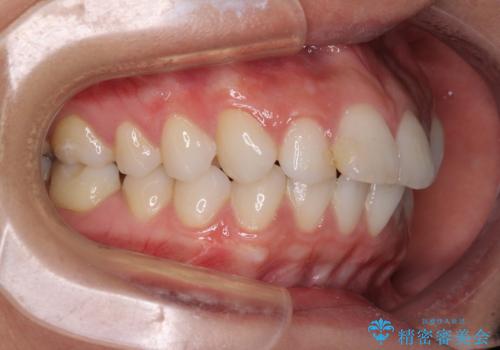

- くちばしのような前歯の突出感を気にして来院された患者様です。

上下左右第一小臼歯4本を抜歯して、積極的に口元を引っ込めるよう、ワイヤー装置にて矯正治療を行うこととしました。

抜歯矯正を行ったことで、顎先のつっぱり感や口元の閉じにくさを解消することができました。